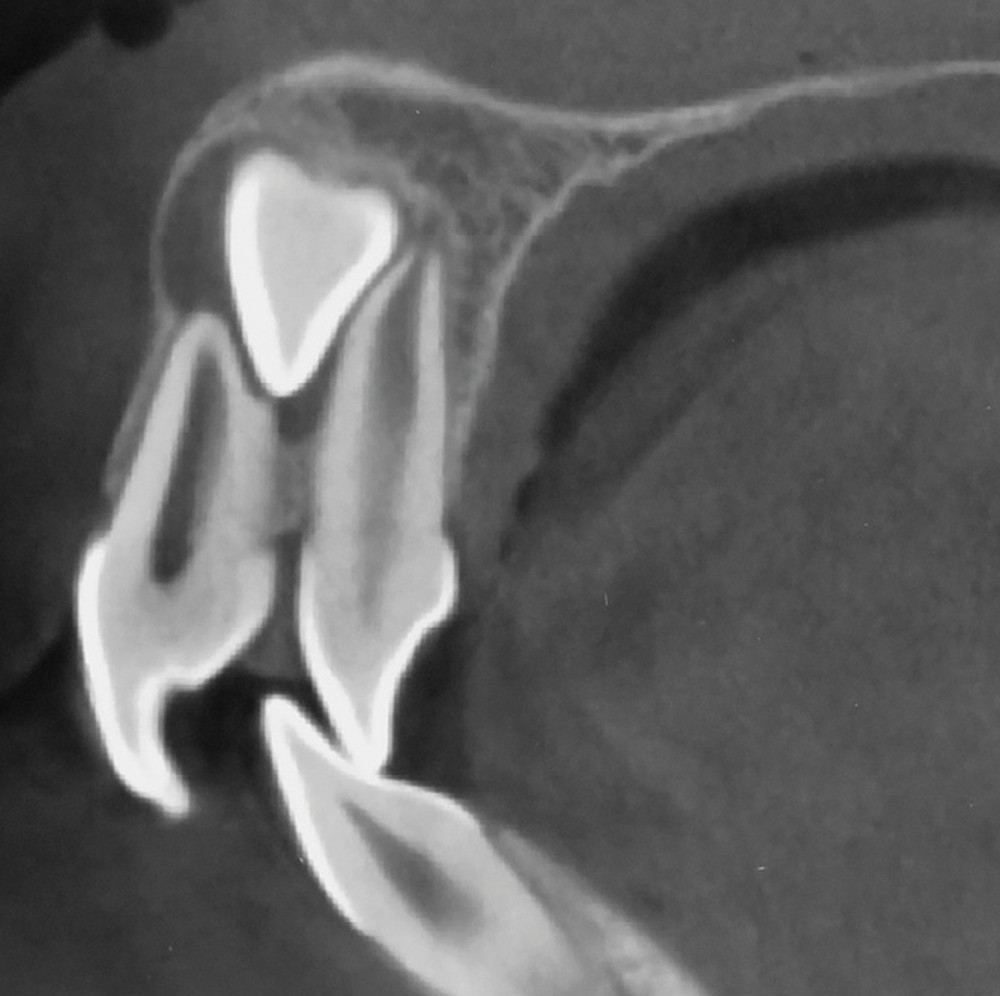

Le profil est convexe et associé à une inocclusion labiale au repos. Il s’agit d’une classe II squelettique sur un schéma facial normodivergent. Les rapports occlusaux sont de classe II bilatérale (complète au niveau molaire) avec des incisives inférieures vestibulo-versées. La 21 est géminée et la 11 vraisemblablement fusionnée avec un germe surnuméraire, sans altération de la formule dentaire. Du fait du diamètre mésiodistal fortement augmenté des incisives centrales, et du manque de place à l’arcade maxillaire qui en découle, les 12 et 22 sont en inversé d’occlusion en palato position. Les 53 et 63 sont persistantes sur l’arcade avec une inclusion en transposition incomplète de la 13, dont la cuspide se situe entre la racine de la 12 et celle de la 11 résorbée (fig. 1d-g).

L’aspect inesthétique des incisives maxillaires (avec une impossibilité de réduction amélaire suffisante du fait des diamètres mésio-distaux radiculaires augmentés) et le pronostic réservé de la 11 (résorption radiculaire marquée) conduisent à la décision d’extraire les deux incisives centrales [1].